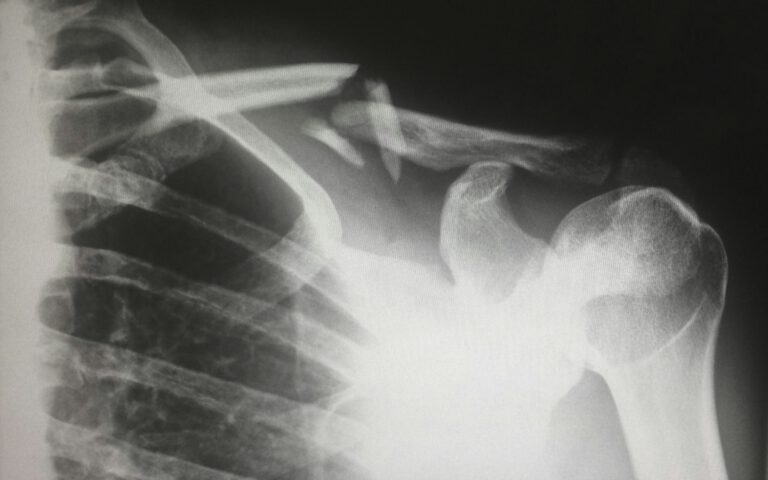

Brüche